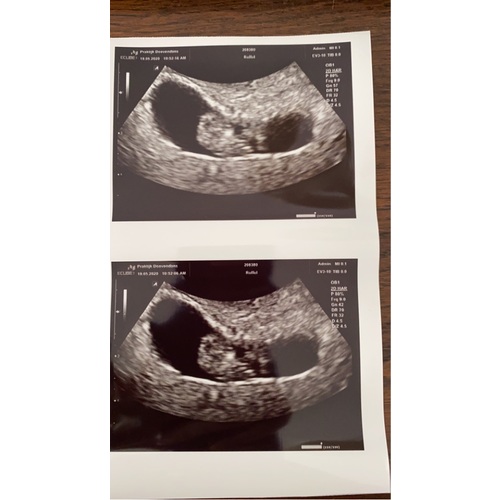

Dit was de mijne met 8+5 😍

Zo zag de mijne eruit 8+ 4